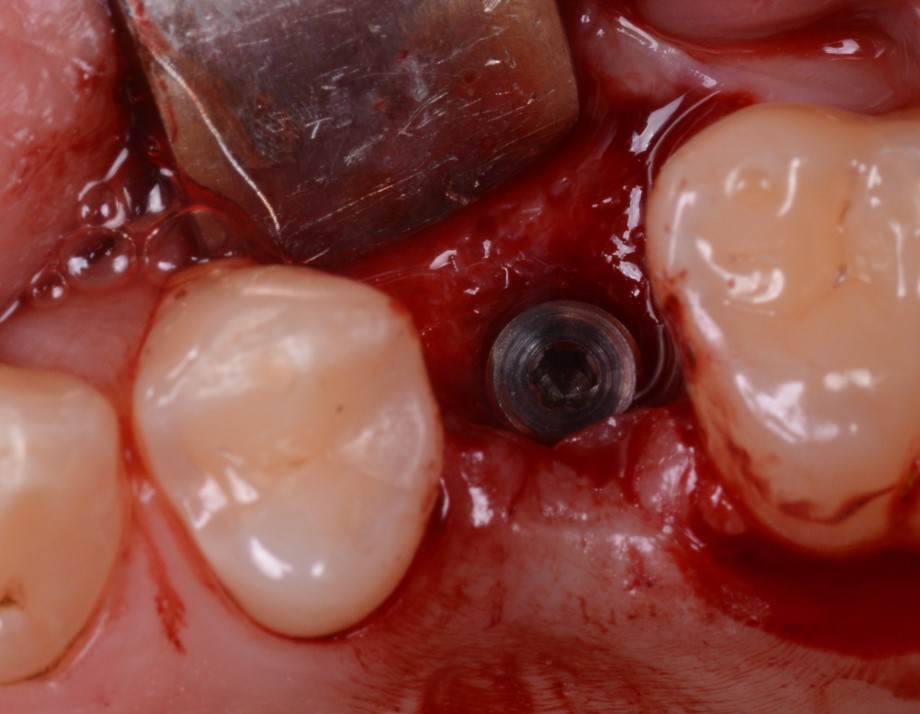

L’impianto prescelto era stampato in 3D (Type K®, AndrewMedical, Carate Brianza, Monza, Italia) con stampante stereolitografica (RenAM 500Q®, Renishaw, Wottonunder-edge, Gloucestershire, UK) e pertanto caratterizzato da una superficie altamente porosa (Fig. 3), in grado di promuovere l’osteointegrazione. Il posizionamento dell’impianto avveniva dopo somministrazione di anestetico locale per infiltrazione, sollevamento di lembo mucoperiosteo a spessore totale, e preparazione del sito con kit implantare dedicato. Inserito l’impianto (Fig. 4), si procedeva a suturare i lembi (Fig. 5).

L’impianto inserito nell’alveolo post-estrattivo

Fig. 4. L’impianto inserito nell’alveolo post-estrattivo.